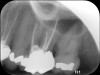

Clinical procedure: If apical bone loss is present (Figure 1) a collagen/gelatin sponge (eg, Gelfoam®, Pfizer Inc., www.pfizer.com) can be placed apically so that the MTA can be delivered to the desired working length. (Any other surgical resorbable sponge would also work, such as OraPlug® [Salvin Dental Specialties, www.salvin.com], Surgifoam® [Midwest Dental, www.mwdental.com], or Surgispon® [Aegis Lifesciences, www.surgispon.com]). This is done by taking a small piece (2 mm x 2 mm) of the resorbable sponge and pushing it down to and through the root apex with an endodontic file. Once this is done, MTA is packed down the canal with a custom-fitted cone. The clinician can use a rubber stopper on the gutta-percha cone to know the exact length of MTA placed in the apical third (Figure 2). Once the apical third is sealed with 3 mm to 5 mm of MTA, the remaining coronal canal space can be back-filled using a warm gutta-percha technique (Figure 3).

Fig 3. Postoperative radiograph.

Figure 3